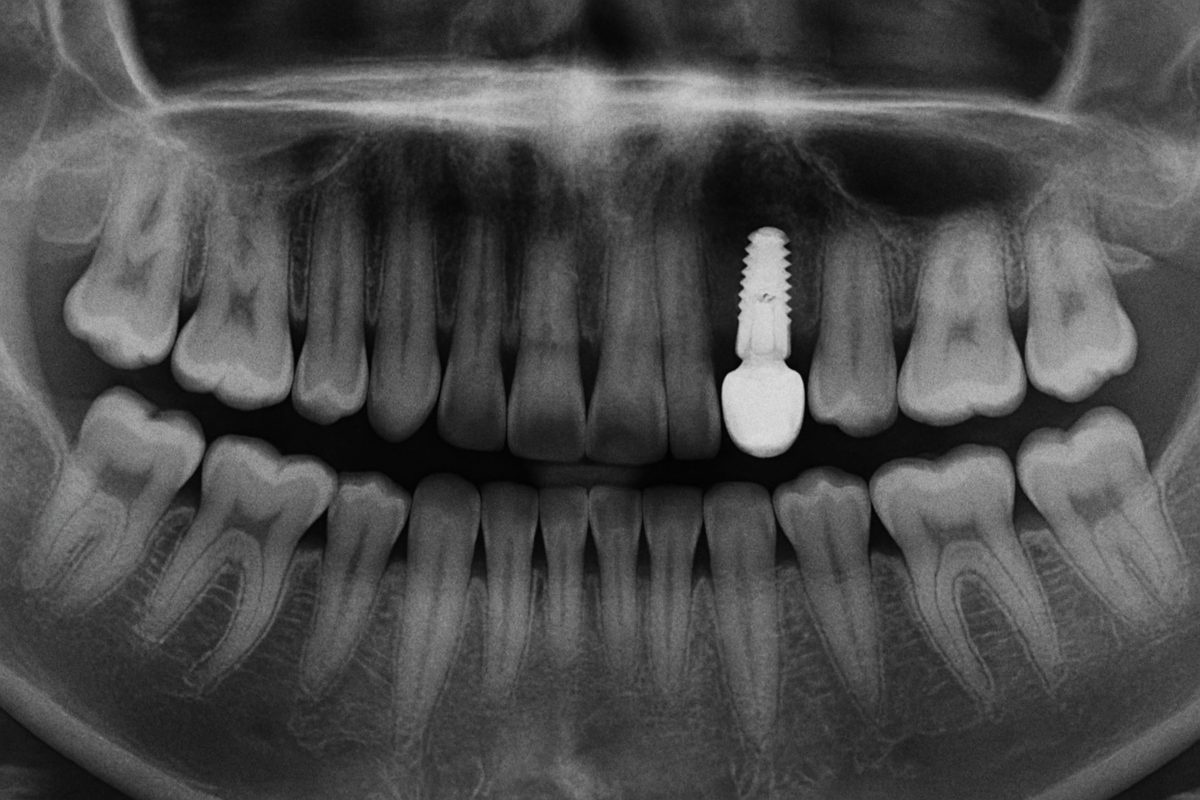

Dental implants are metal posts placed into the jawbone to replace missing teeth. Most people heal over weeks to months as the bone fuses to

Single Dental Implants: The Most Reliable Way to Replace a Missing Tooth If you’re missing a tooth — whether due to decay, trauma, or gum

Many patients ask, “how do implants work” when they first consider replacing a missing tooth. This short guide explains the basics in plain language, walks

The parts of a tooth implant can seem complex, but knowing the main pieces helps you understand treatment, care, and how implants restore function. This

Finding the best deal on dental implants means more than picking the lowest price. Dental implants replace missing teeth with a titanium post, an abutment,

If you’re reading about dental implants, this guide will walk you through what they are, who makes a good candidate, the step-by-step process, recovery tips,